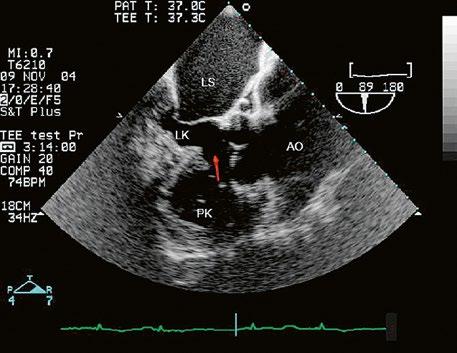

Obr. 45.1 Defekt septa síní typu II v TEE

AO – aorta, DDŽ – ústí dolní duté žíly do pravé síně, defekt septa síní je označen křížky, má předozadní průměr 22 mm, zasahuje blízko zadní stěny levé síně, LS – levá síň, PS – pravá síň

Obr. 45.2 Defekt septa síní typu II v TEE

AO – aorta, ASD – defekt septa síní typu secundum označen šipkou, zelenými křížky je označen malý přední rim k aortě, LS – levá síň, PS – pravá síň